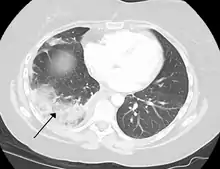

Cancers

Lung cancer can either arise directly from lung tissue or as a result of metastasis from another part of the body. There are two main types of primary tumour described as either small-cell or non-small-cell lung carcinomas. The major risk factor for cancer is smoking. Once a cancer is identified it is staged using scans such as a CT scan and a sample of tissue from a biopsy is taken. Cancers may be treated surgically by removing the tumour, the use of radiotherapy, chemotherapy or a combination, or with the aim of symptom control.[73] Lung cancer screening is being recommended in the United States for high-risk populations.[92]